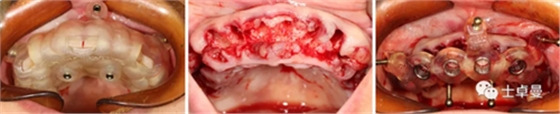

外科手術(shù)過程

上頜種植手術(shù)

常規(guī)消毒碧藍麻局麻下,利用牙支持式導板確定固位釘位置后取下導板;

然后分離牙齦,于牙槽嵴頰腭側(cè)略翻瓣暴露牙根與牙槽骨間隙,切除齦瓣邊緣炎性肉芽組織,拔除上頜16-27牙,球鉆清理拔牙窩,并用大量生理鹽水沖洗;

通過先前固位釘位置安放固位釘支持式種植導板,因拔牙前后軟硬組織變化較大,需耐心尋找先前固位釘位置;

導板就位后利用Straumann BLT全程導板工具盒全程備洞,取下導板后利用測量桿確認種植體窩方向和深度以及種植窩周圍骨量;

植入6顆Straumann BLT種植體,植入扭矩均達到45Ncm以上:

16、26:4.1mm×14mm

14、24:4.1mm×12mm

12、22:3.3mm×12mm

安裝SRA基臺,均加力至35Ncm:

16、26:RC30°4mmA型

14,24:RC17°2.5mmA型

12,22:NC17°2.5mmA型

旋入SRA基臺保護帽,修整粘膜,縫合。

a10.png